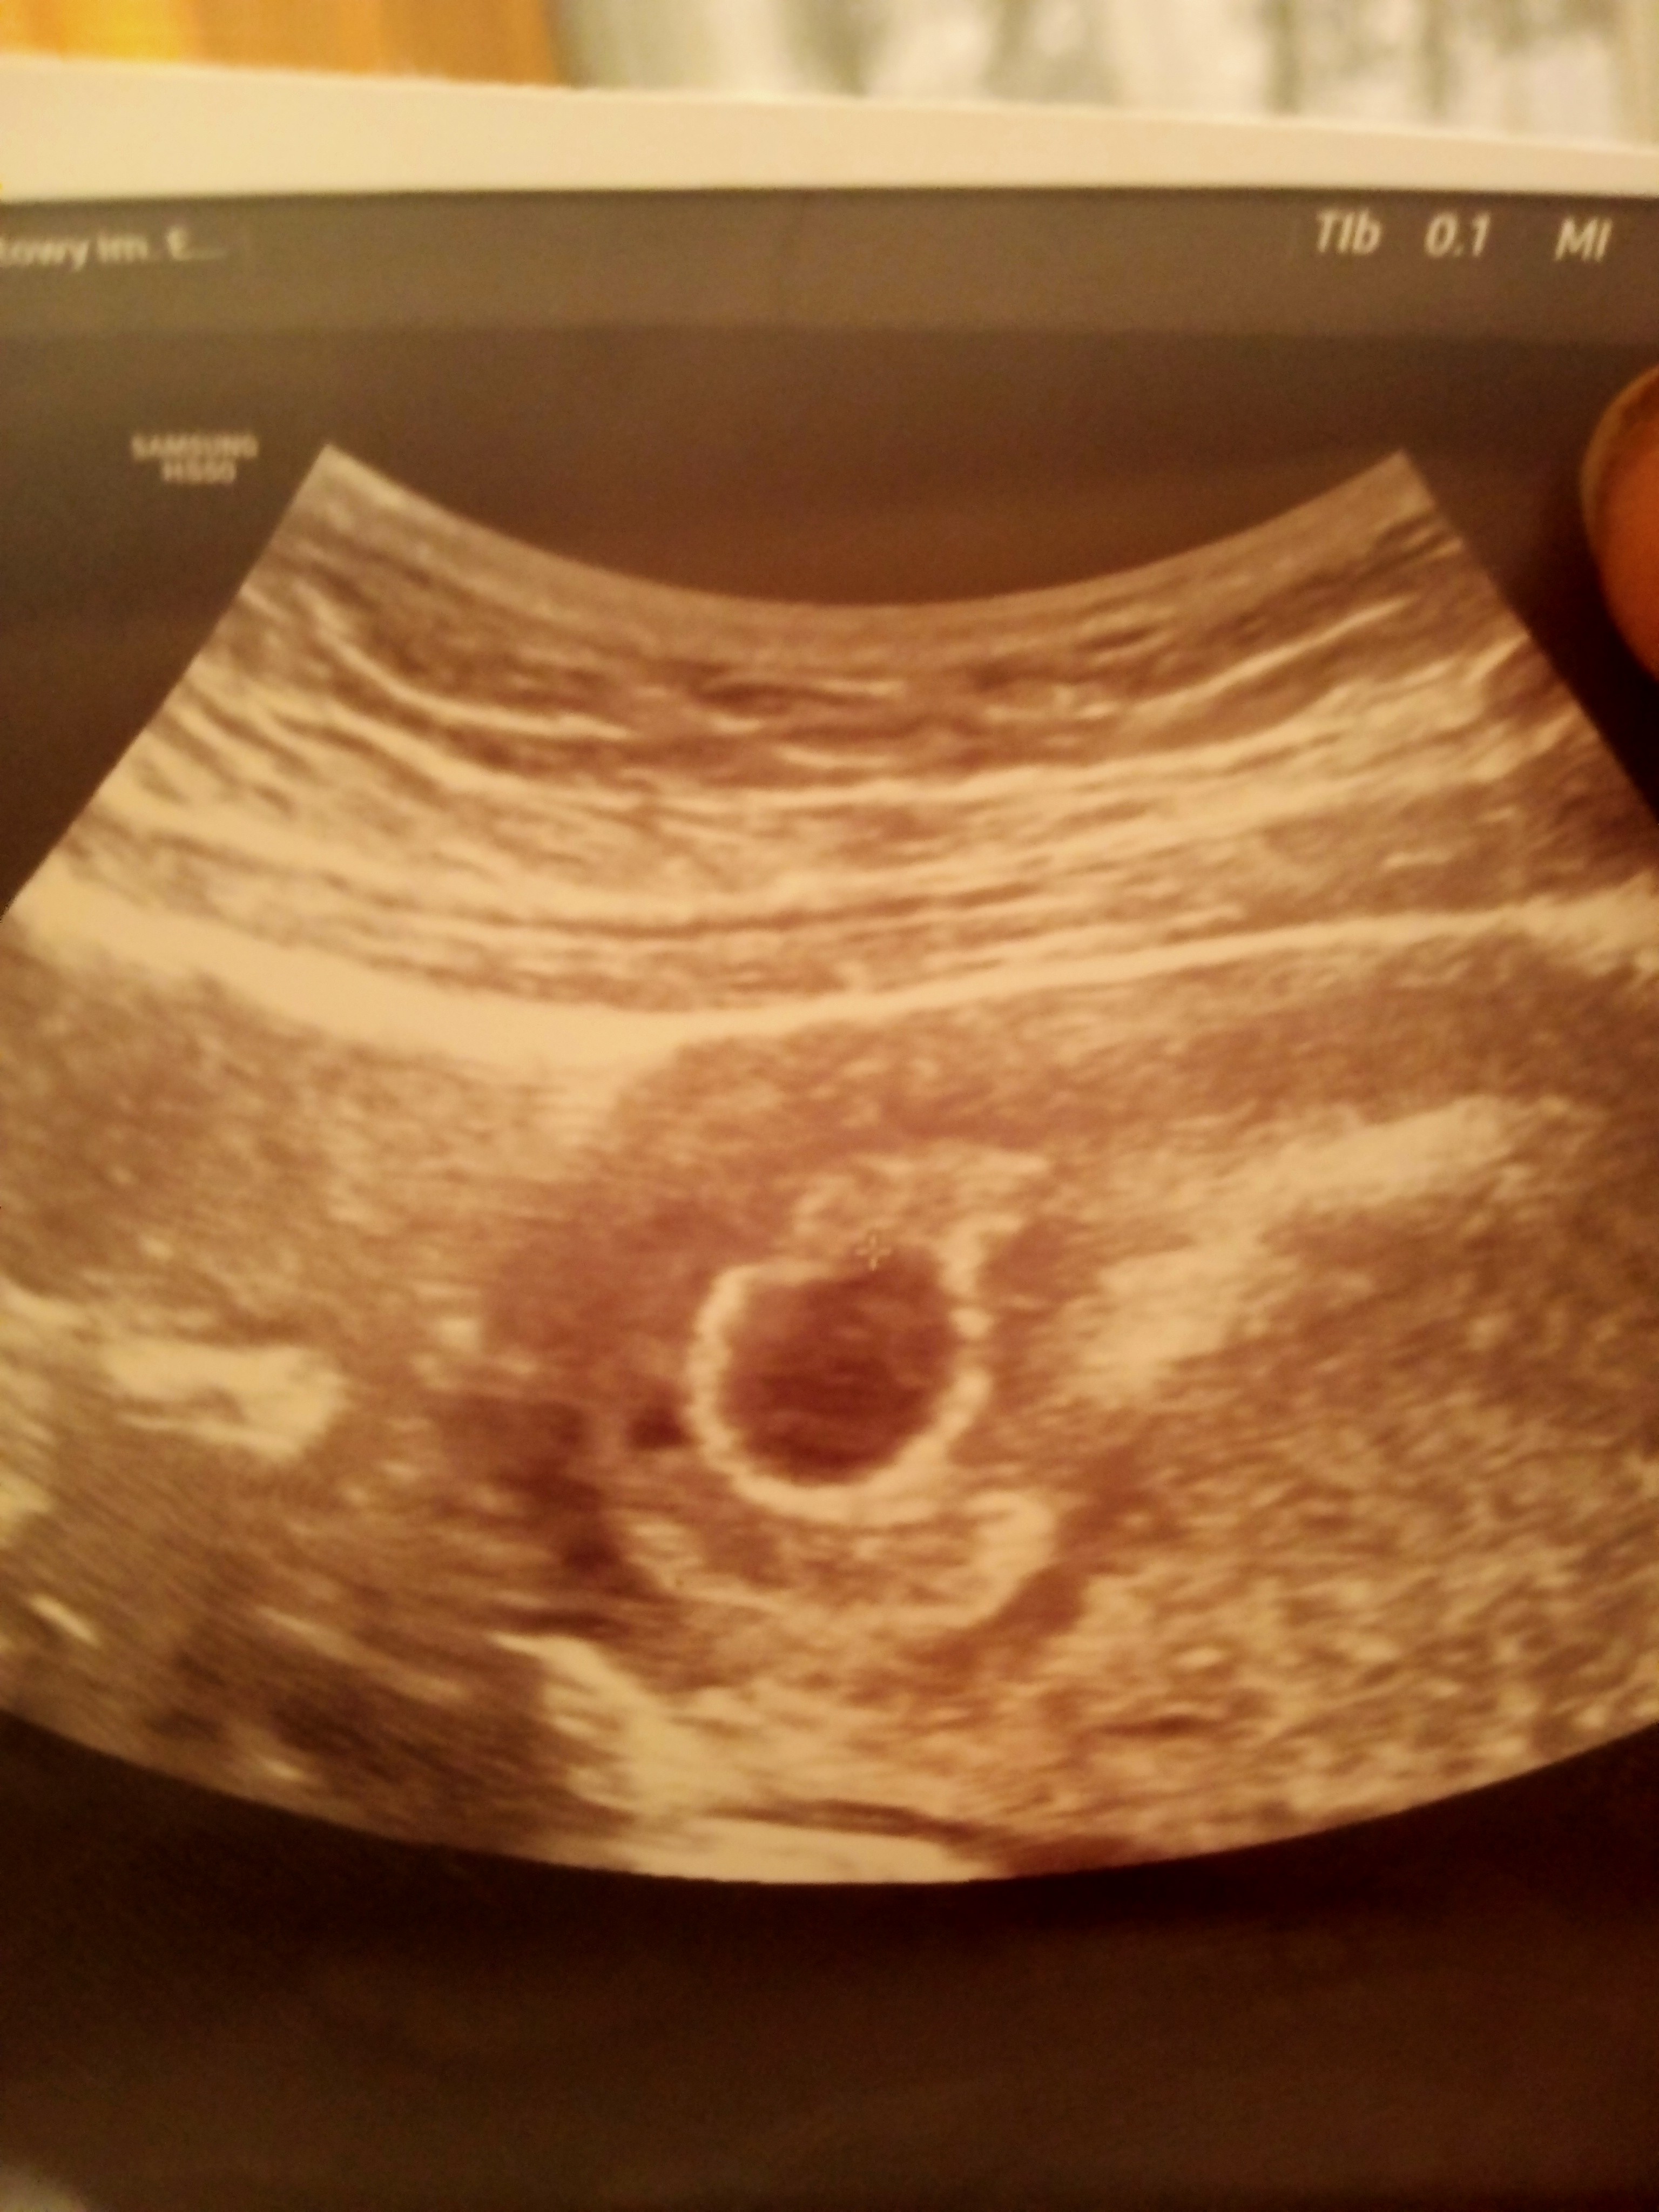

Dziewczyny czy miałyście tak że według ostatniej miesiączki jestem w 6 tygodniu , i lekarz powiedział że echo zarodka słabo wyczuwalne czy mam się bać ? Czy po prostu może okazać się że ciąża jest młodsza ? Lekarz nie powiedział mi nic konkretnego tylko tyle że musimy teraz patrzeć jak to będzie się rozwijać

Słabo widoczne przepraszam

Jeśli owulacja nie była monitorowana to mogła być później, a mogło być też tak, że zagnieżdżenie było późno. Nie ma się co martwić niepotrzebnie.

Właśnie narazie nie biorę tego pod uwagę cieszę się że jest moja gwiazdeczka ❤️ bo we wtorek byłam u innego lekarza to powiedział mi że podejrzewa puste jajo aż mnie coś skręcało mówię nie możliwe , cała noc się martwiłam a wczoraj dowiedziałam się że jest ❤️ zobaczcie jaką jest różnica sprzęt a sprzęt 😊 we wtorek było robione USG normlanie a z wczoraj jest dopochowo